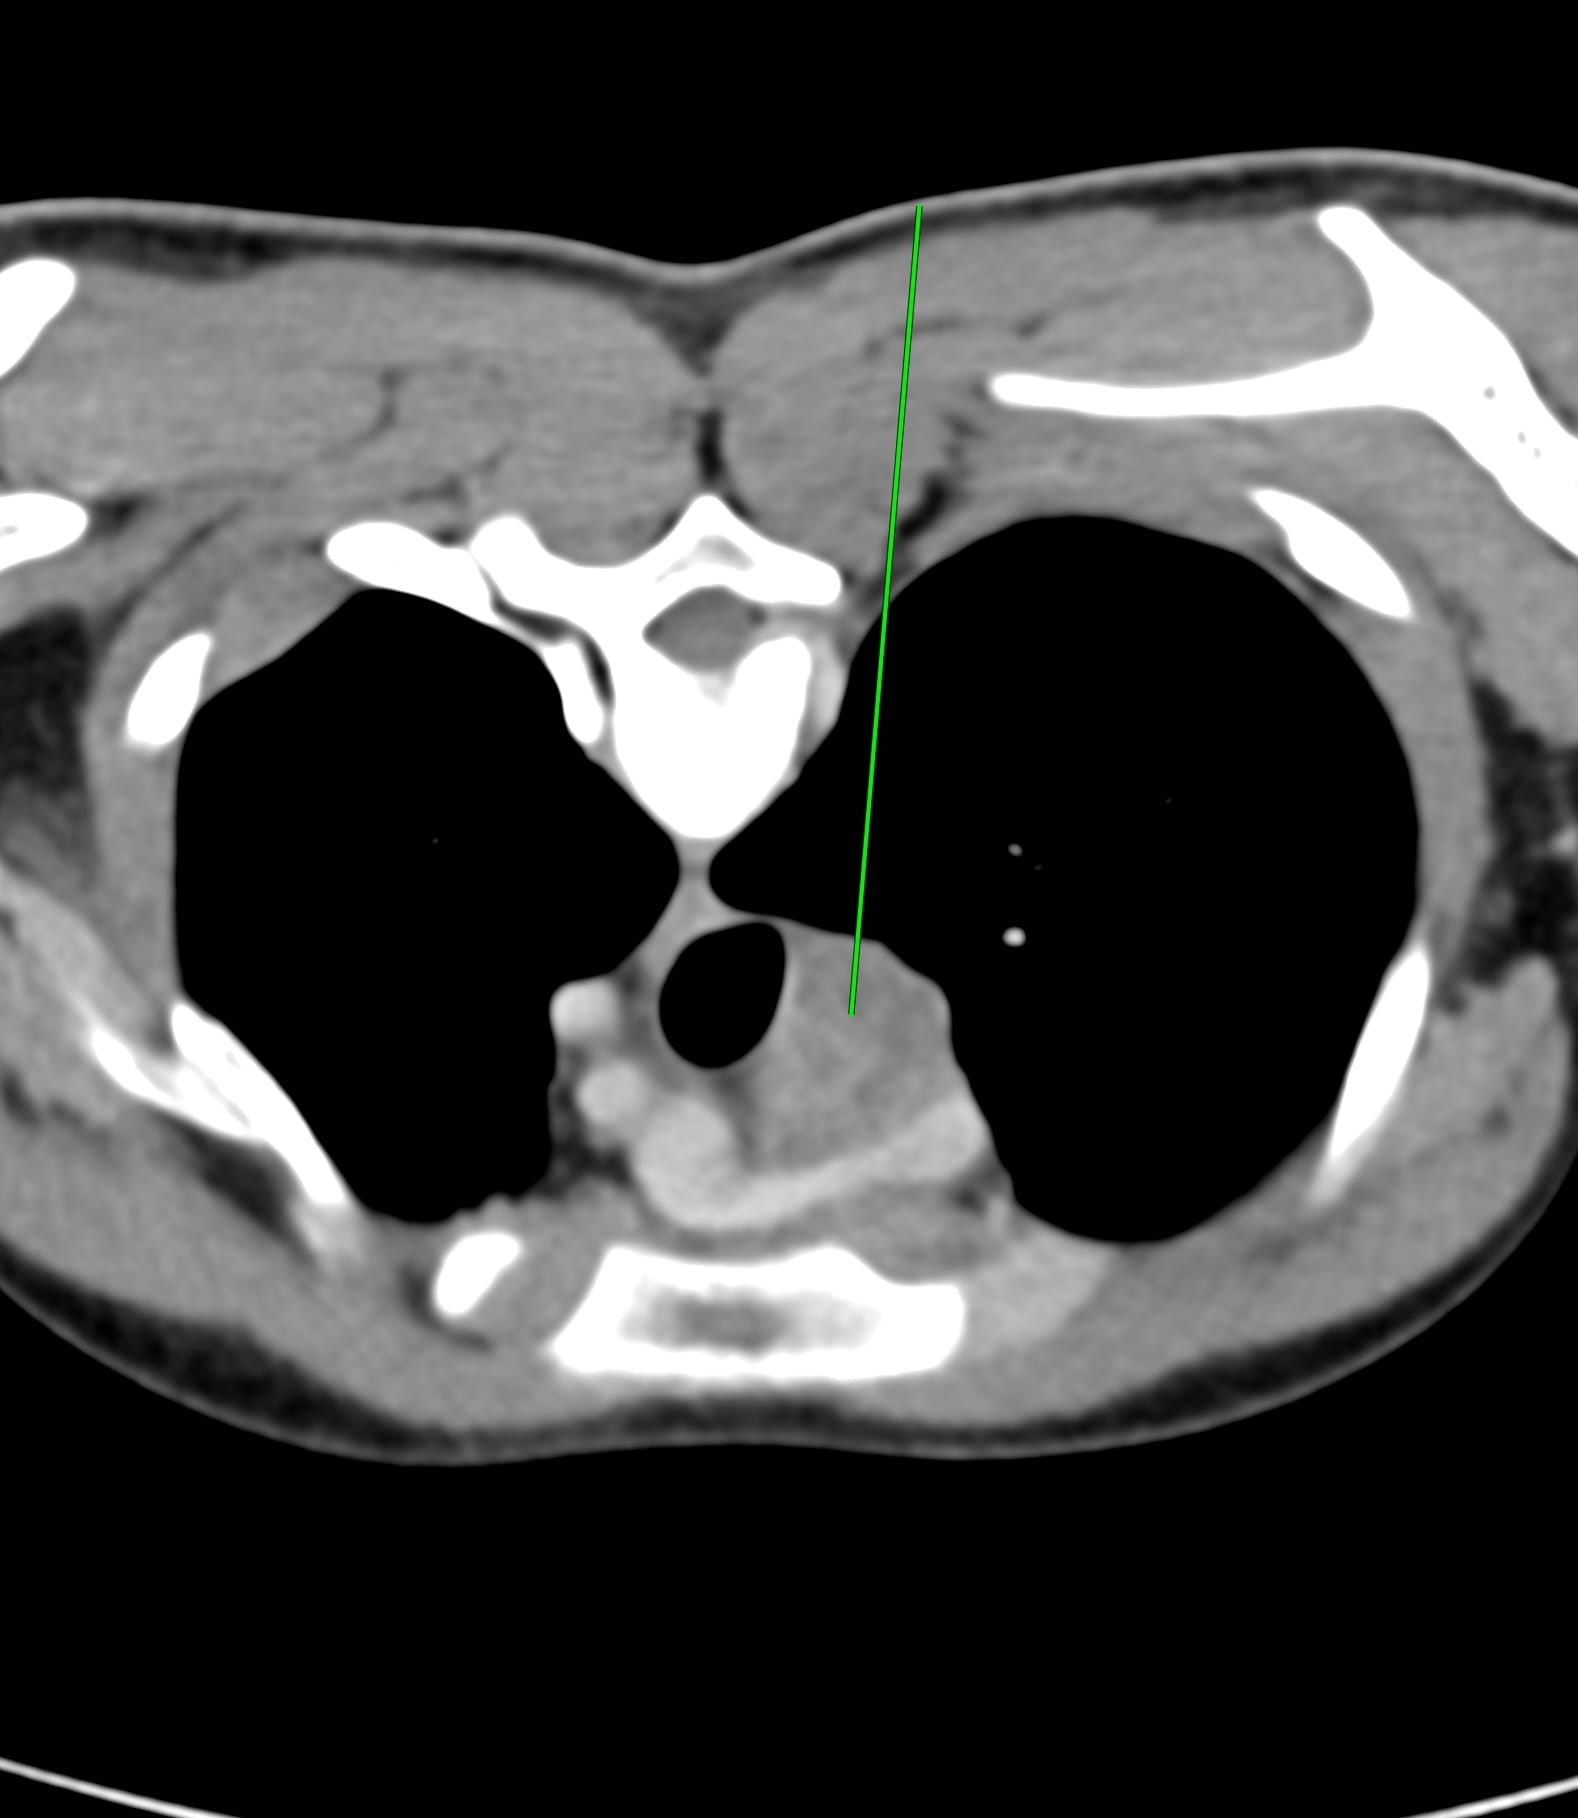

While an extrapleural biopsy with hydrodissection is what I usually do, in this case, the lung was extending more medially and a transparenchymal route made more sense.

The next figure shows the procedure. An 18G BARD needle was introduced into the clear space next to the foramen (A) and 10 cc of lignocaine was injected just over the pleura (B). The needle was then passed through a sliver of the lung (C) and then through it into the node (D). 5 cc of pus was aspirated and then intravenous contrast was given before deploying the gun - a hub was used to deploy only 10 mm so as not to overshoot (E). The rapid rollover (F) shows no pneumothorax or hemorrhage. It took 11 minutes.

In the young, it is rare to get a pneumothorax when going through otherwise normal lung and unless you go through a big vessel, hemorrhage is also unlikely. The only thing to take care of is not to overshoot into the mediastinal vessels.